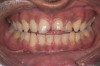

A 20-year-old male patient presented with irregular upper anterior teeth and was unhappy with his smile (Figure 4). He complained of occasional generalized mild sensitivity. Dental treatment history revealed that he had occasional dental work done in the past. Two weeks previously, he had severe pain in tooth No. 10, which was treated endodontically, and he was then referred to the author’s practice for management of anterior wear. Tooth No. 3 had a broken amalgam restoration.

Examination revealed that palatal surfaces of teeth Nos. 6 through 11 showed severe loss of tooth structure, with mild wear on the lower incisors and loss of anterior guidance (Figure 5 through Figure 7). The palatal TSL was consistent with the clinical picture presented by patients with gastric reflux. A detailed medical history was taken, and the patient complained of having heartburn and acidity at least 4 out of 7 days a week. He had never sought treatment for it and used over-the-counter medication when needed. He was a nonsmoker, with occasional intake of alcohol. He had a high-stress job with irregular meal times. A thorough smile and dental analysis11 was carried out; the findings appear in Table 2.